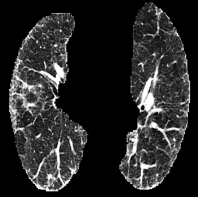

Based on Eqn. (2), we can identify the most influential cluster contributing to the final score for each individual by vectorizing the feature for each cluster. The heatmap in Supplementary Fig. 2 represents the contribution of the cluster to the final patient-level risk score on the FLD dataset, where the panels from left to right depict the vectors for patients arranged in decreasing order of value. The rationale behind each patient’s final prediction: the red cube highlights clusters contributing to high-risk scores, while blue indicates a lower risk. From this visualization, we can see that patients with different prediction results are highly disentangled, and the contributing patterns are clearly delineated for each patient. The most influential clusters across the dataset are determined by comparing the average values between the two classes with different predictions. The ranking of clusters by contribution to the ‘mortality in one year’ class on the FLD dataset is shown in Supplementary Fig. 3 and the most representative slice patterns are provided in Supplementary Fig. 4, which show that the model can identify common clusters within each class group, enabling us to pinpoint most significant features by visualizing the most frequently contributing clusters among patients.

Cluster 5